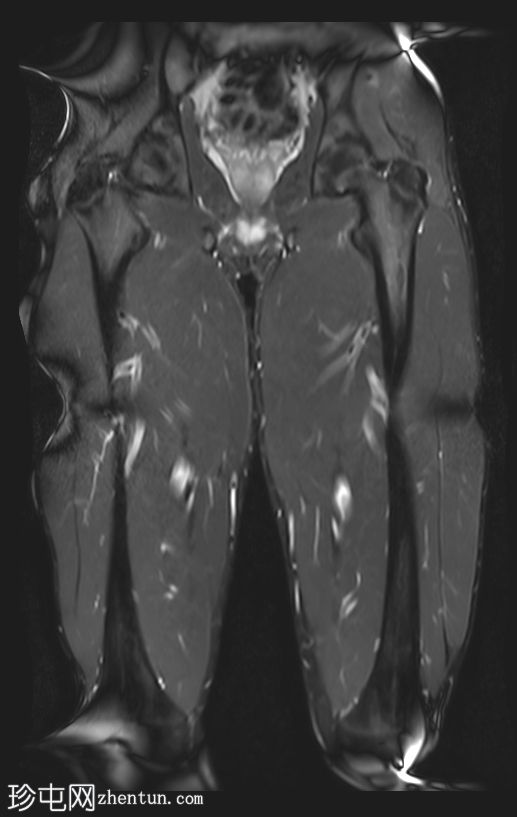

轴位

STIR序列

股二头肌长头近端和中段可见高信号水肿,大小约10×3厘米。

此外,邻近的半腱肌可见羽毛状水肿,大小约5×2厘米。

未见肌内积液或血肿。

邻近肌间隙可见一条粗液线,延伸至近端和远端肌腱连接处。

股二头肌腱近端和中段轻度增厚,呈波浪状轮廓,腱周积液延伸至肌腱连接处。然而,未发现撕裂。